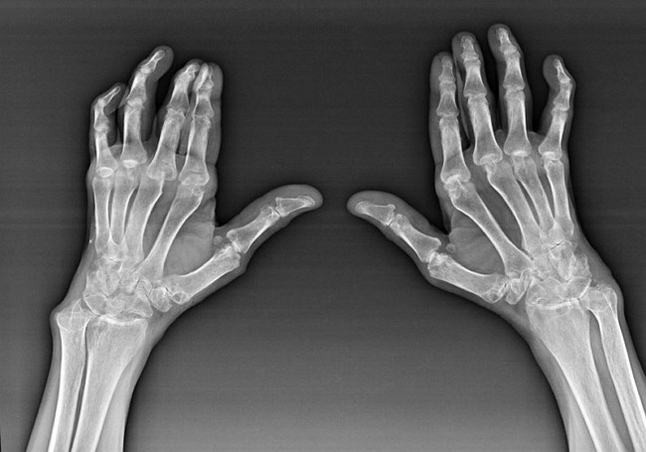

Artrite reumatoide

A artrite reumatoide é unha enfermidade na que o sistema inmunitario humano dana os tecidos propios do corpo. Noutras palabras, a artrite reumatoide é unha patoloxía autoinmune. Esta enfermidade tamén é sistémica, xa que moitos tecidos están afectados con ela (músculos, articulacións, buques, etc.) e órganos (Corazón, riles, pulmóns, etc.) no corpo.

A pesar de que a artrite reumatoide é unha enfermidade sistémica baixo ela, en maior medida, as articulacións sofren, mentres que a lesión doutros tecidos e órganos está nun segundo plano. Con esta enfermidade, case todo tipo de articulacións de cepillos poden verse afectadas (Mulleres de pulsera, camiños carpianos, metacarpal-falanx, xuntas inter-falanxes). A lesión adoita ser simétrica (eses. As mesmas articulacións están afectadas) en ambas as mans, acompañado de inchazo, dor nas articulacións danadas. Pola mañá, durante o levantamento da cama, hai algo de rixidez nas articulacións afectadas, que pode durar aproximadamente 1 hora e logo desaparecer sen rastro.

A miúdo con artrite reumática preto das articulacións afectadas do cepillo (Moitas veces a piano-falánx, articulacións inter-falanxes) Aparecen nódulos reumatoides. Son unha formación redondeada situada baixo a pel. No cepillo, estas formacións xorden máis a miúdo na parte traseira. Na palpación, son densos, inactivos, indoloros. O número deles pode variar.